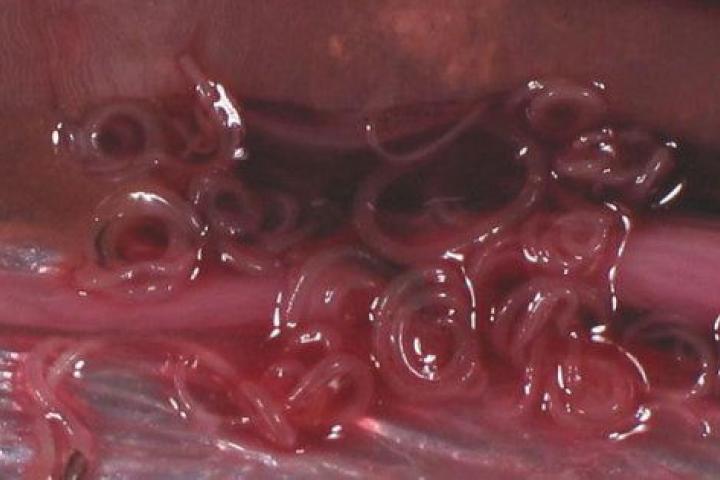

España se sitúa después de Japón como el país con mayor número de intoxicaciones por anisakis, un parásito que se transmite a los seres humanos a través de la ingestión de pescados o cefalópodos contaminados y que provoca trastornos gastrointestinales y alérgicos.

Uno de cada tres pescados que se consumen en España está infectado

Uno de cada tres pescados que se consumen en España está infectado. Se producen 8.000 casos al año, sobre todo en Euskadi, Madrid, Cantabria y Andalucía.

Si bien el porcentaje de muestras afectadas es muy variable según la zona de origen y la época del año, los pescados más frecuentemente parasitados son la merluza y el bonito, pero los boquerones y anchoas provocan más intoxicaciones en España.